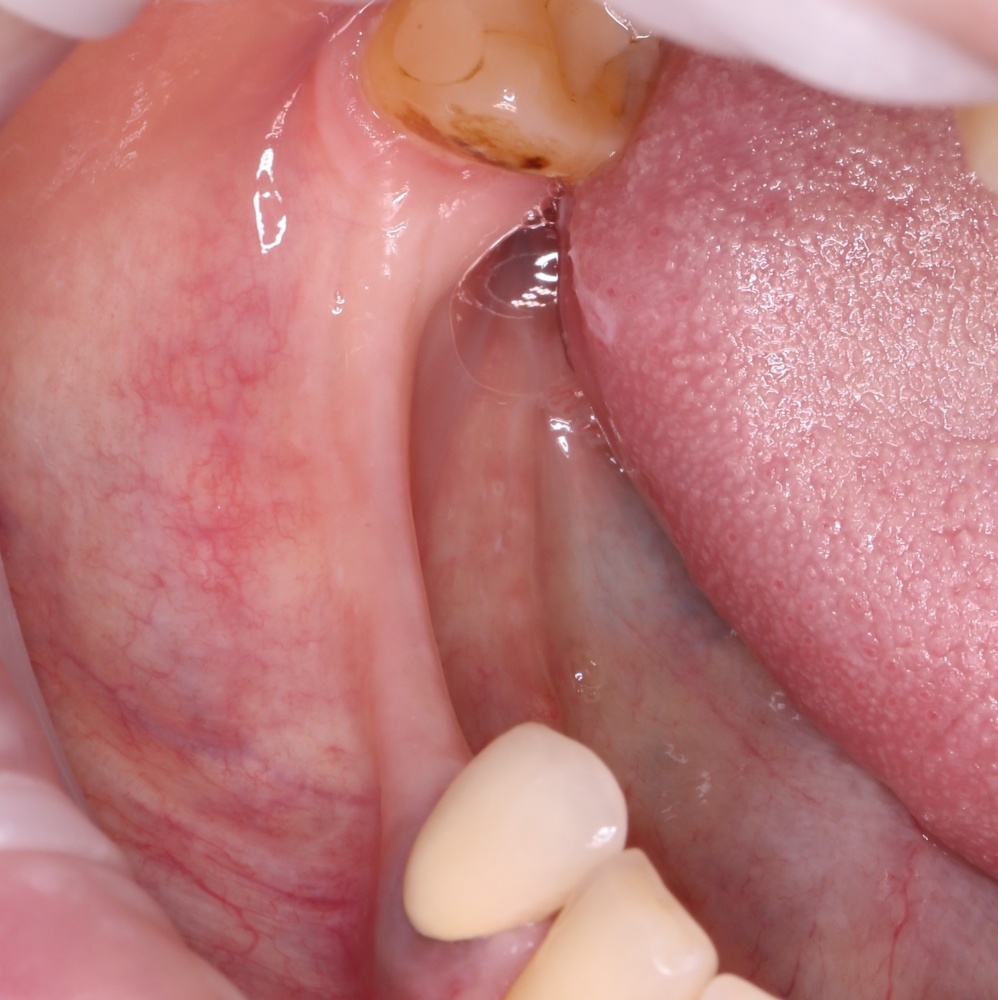

Рекомендации по установке имплантов. Для всех. Часть V.